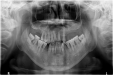

【科室概况】济南市口腔医院医学影像科于1956年开展放射诊断业务,1963年成立X光室,2009年更名医学影像科,为中华口腔医学会口腔颌面放射专业委员会委员单位,现有影像诊断主治医师2名,副主任技师1名,硕士研究生3名,参与编著《口腔颌面影像医学》教材一部。拥有国内先进的大视野New-Tom CBCT一台,三合一CBCT八台,数字牙片机九台,直接数字化X射线摄影系统(DR)一台。【服务范围】CBCT:具有完善的三维重建功能,主要用于种植牙术前评估,正畸测量...